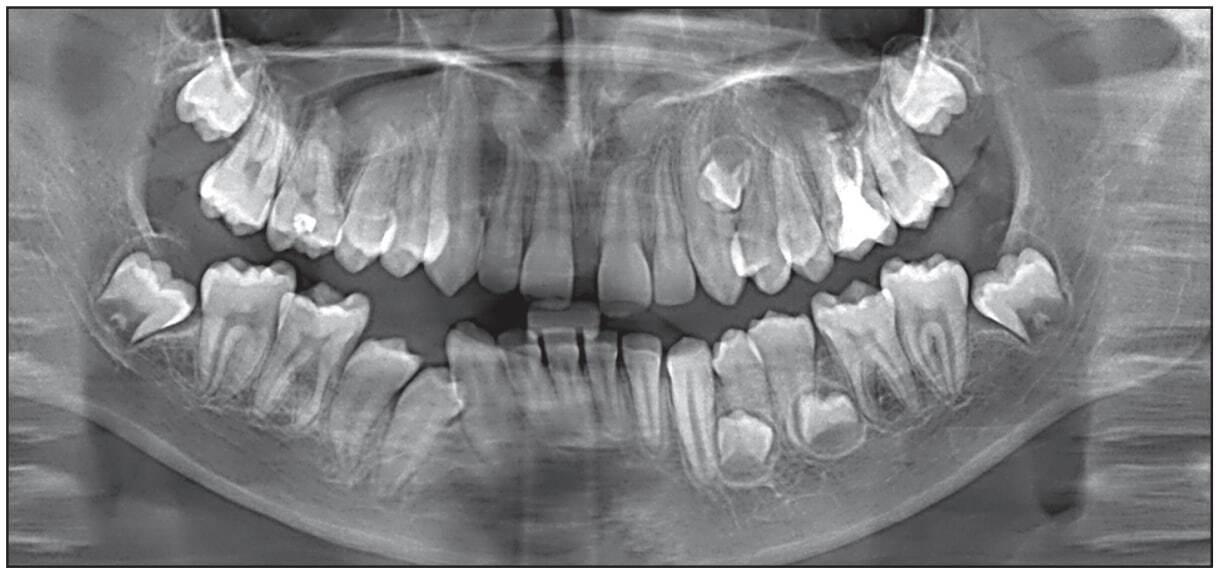

С предварительным диагнозом «ретенция 1.1, 2.1, 2.4, 3.4, 3.5, 4.4, 4.5 зубов, сверхкомплектные зубы» пациент направлен на ортопантомографию челюстей. На ортопантомограмме (рис. 2) патология костной ткани отсутствовала.

Рис. 2. Ортопантомограмма Ф. А., 10 лет, до лечения

Выявлены зачатки 1.1, 2.1, 2.4, 3.4, 3.5, 4.4, 4.5, корни которых находятся в стадии апексогенеза. Количество сверхкомплектных зубов на ортопантомограмме точно определить не удалось. Наклон ретенированных постоянных зубов был разнообразным. Конвергенция зубов, ограничивающих дефекты зубных дуг, и дефицит места в дуге препятствовали прорезыванию ретенированных зубов в дугу. По результатам клинических и рентгенологических методов исследования сформулирован диагноз «дистальная окклюзия, глубокая резцовая дизокклюзия; сужение и укорочение зубных дуг, тесное положение зубов; ретенция 1.1, 2.1, 2.4, 3.4, 3.5, 4.4, 4.5 зубов; ретенция сверхкомплектных зубов». Комплексный план лечения включал ортодонтические и хирургические вмешательства. Ортодонтическое лечение было начато с создания места в зубной дуге для прорезывания ретенированных центральных резцов верхней челюсти при помощи небной пластинки с расширяющим винтом и искусственными резцами. Хирургическое вмешательство включало удаление сверхкомплектных зубов в области 1.1, 2.1 зубов. Через шесть месяцев началось прорезы вание 1.1 и 2.1 зубов. В этой связи искусственные резцы были сошлифованы, съемный аппарат оставлен для сохранения места в зубной дуге для прорезывания резцов. Для оценки эффективности результатов проведенного лечения и уточнения плана лечебных мероприятий пациент был повторно направлен на ортопантомографию (рис. 3), для уточнения ситуации – на компьютерную томографию челюстей, по результатам которой выявлены пять сверхкомплектных зубов, в том числе в области верхних клыка и первого премоляра слева – один, нижних премоляров слева – два, нижних премоляра справа – два.